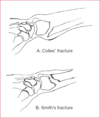

Colles Fracture

Distal radius fragment is dorsally displaced (CD). Associated with triangular fibrocartilage complex (TFCC) tears.